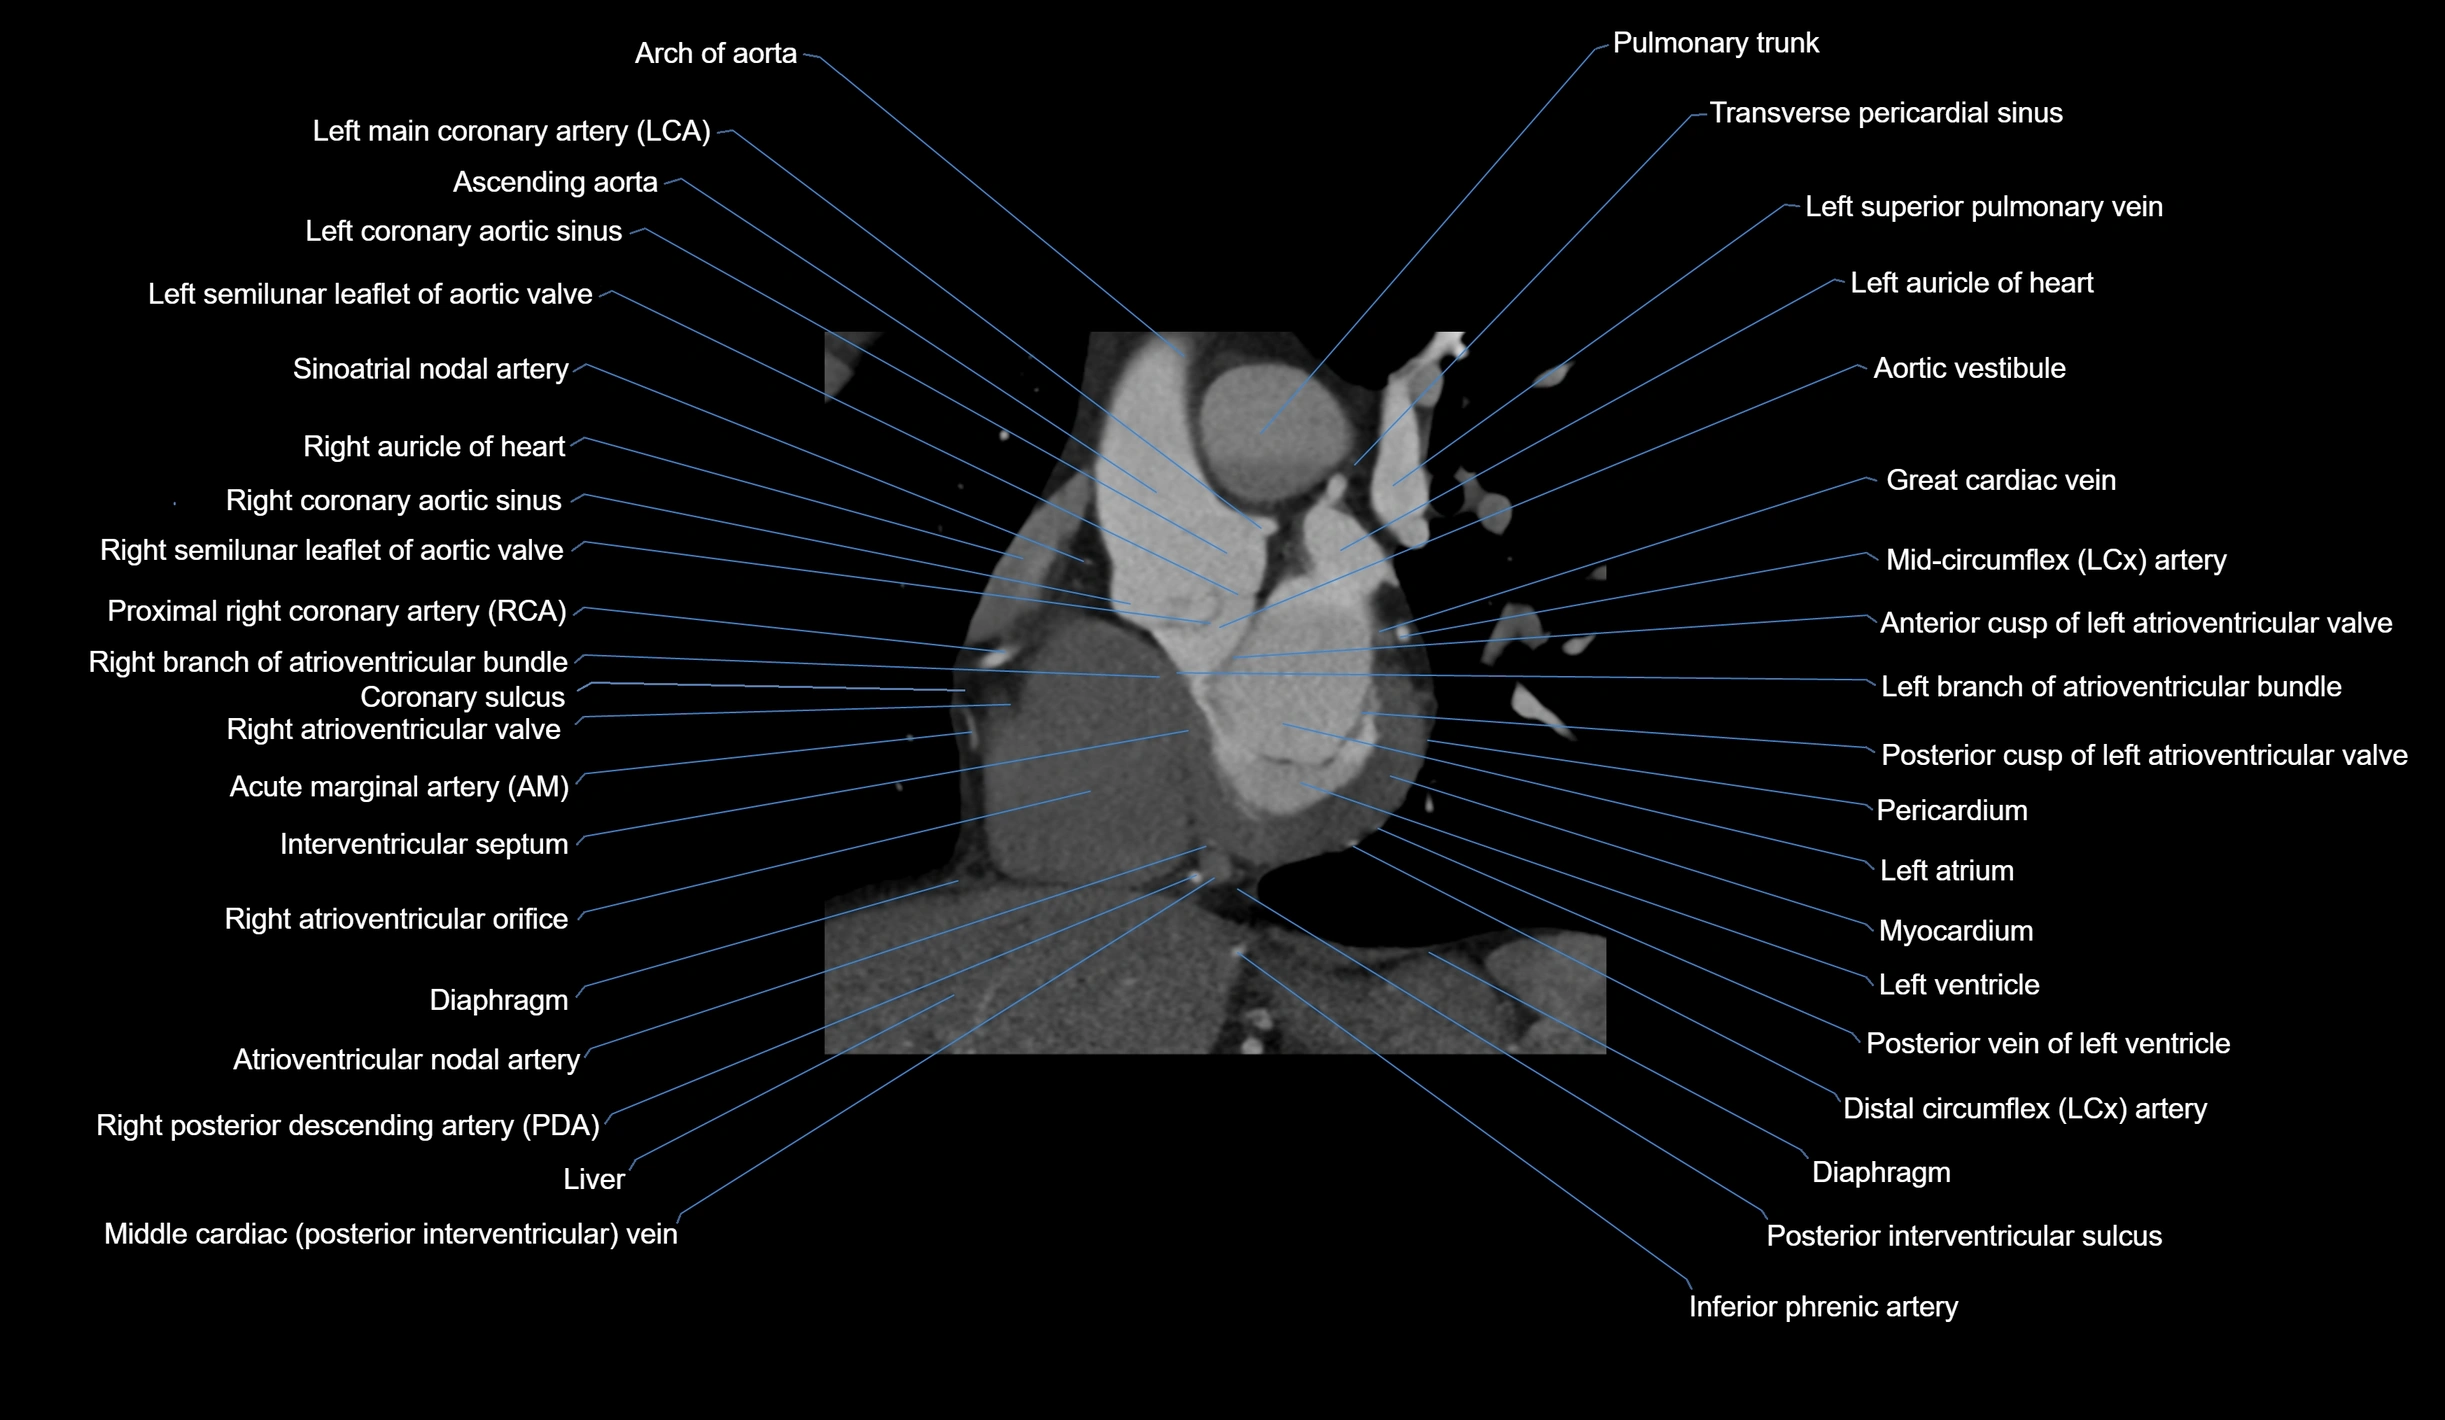

CT images